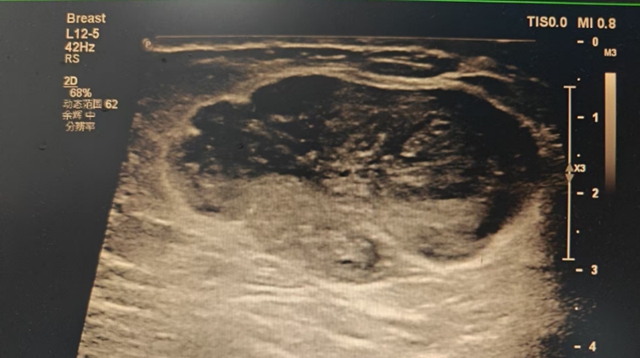

随即,杨女士便到当地医院进行了检查,检查结果让其震了一下。乳腺彩超提示“左侧乳腺低回声团,拟US-BI-RADS-4b类”(提示可能为恶性)。为求进一步诊治,她来到西南医科大学附属中医医院乳腺·甲状腺·血管外科就诊。

科室冷婕副教授接诊后,结合杨女士带来的彩超报告及查体结果,高度怀疑为乳腺肿瘤。为了明确性质,冷婕为杨女士进行了空芯针活检,病检结果提示:交界性分叶状肿瘤。